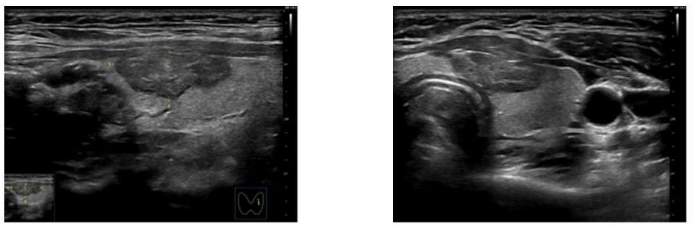

甲状腺左侧叶近峡部结节